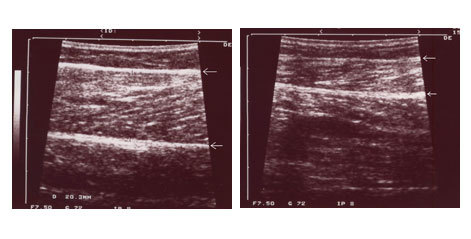

病例八:下圖病例術前小腿圍為36公分(左圖),做完腓腸肌及比目魚肌部份切除手術及小腿抽脂後三週,小腿圍已經變為32公分(右圖)。膝蓋後方的疤痕會漸漸變淡。下左圖是病人術前內側腓腸肌的超音波圖,二個箭頭間是內側腓腸肌,有二公分厚。

術後檢查內側腓腸肌變為一公分(下右圖)。